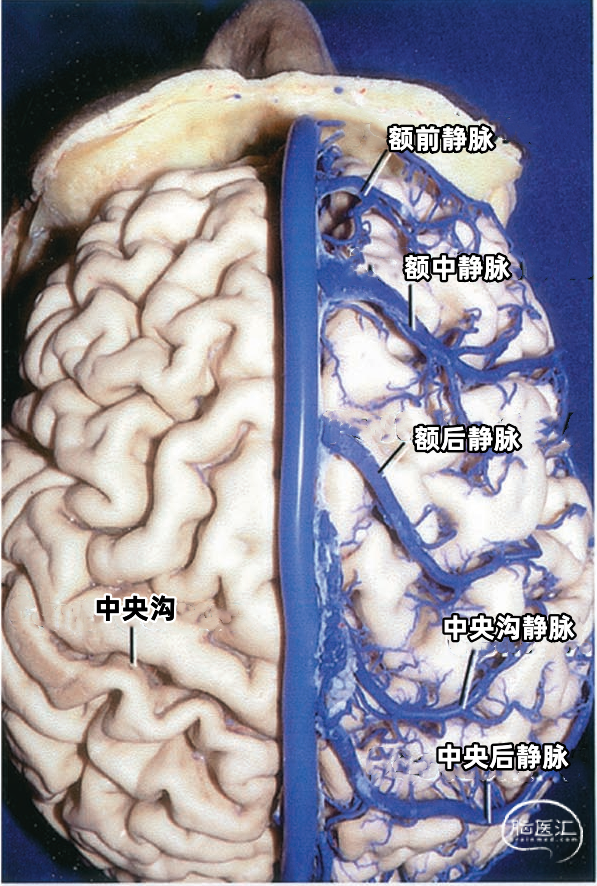

从两侧皮层汇入上矢状窦的皮层静脉具有特有的形态(下图)。左侧显示汇入上矢状窦的静脉,右侧显示静脉入窦的平均角度。从前到后,静脉入窦的角度逐渐减小。 额极附近的静脉,与上矢状窦内血流方向一致,汇入上矢状窦; 额叶后部的静脉向前汇入上矢状窦,与窦内血流的方向相反; 顶叶和枕叶的静脉向前汇入上矢状窦,与窦内血流方向相反;| 额极静脉 110° | 额前静脉 110° |

| 额中静脉 85° | 额后静脉 65° |

| 中央前静脉 50° | 中央静脉 45° |

| 中央后静脉 40° | 顶前静脉 25° |

| 顶后静脉 15° | 枕静脉10° |

皮层静脉可直接入上矢状窦,也可经过硬膜窦引流入上矢状窦。额前部和顶后部外侧面的静脉回流倾向于加入上矢状窦旁的硬膜窦。额后部和顶部的静脉通常经静脉腔隙下面直接进入上矢状窦。 直接入窦的皮层静脉可进入窦的外侧角、外侧壁或下角,皮层静脉在入窦前可能先与窦外侧壁粘连,静脉与窦壁粘连的长度各异,最靠后的静脉最长,可达8cm。 其他皮层静脉在离矢状窦0.5~3.0cm的凸面加入硬膜窦,这些硬膜窦行向内侧进入上矢状窦外侧角。 数条皮层静脉可加入一个硬膜窦,2~3个硬膜窦可在到达上矢状窦前形成一个前庭。

下图示右侧额中静脉、额后静脉先进入靠近上矢状窦的硬膜窦。然后再进入矢状窦。额前静脉直接引流入上矢状窦。黄色箭头所指为硬膜窦,右侧有2个,左侧有3个。

下图示左侧额前、额中,额后静脉和中央前静脉不直接进入上矢状窦,而是进入额叶上缘的硬膜窦,然后进入上矢状窦。黄色箭头指示左侧的4个硬膜窦。

静脉腔隙(Venous lacunae),也称为静脉湖、静脉间腔、静脉间隙,来自硬脑膜的引流静脉在上矢状窦附近扩大形成静脉腔隙,它位于两层硬脑膜之间(下图)。 静脉腔隙主要接受硬脑膜内硬脑膜静脉的回流,也引流板障静脉的血液。 静脉腔隙内壁有蛛网膜颗粒(上图),进入上矢状窦的皮层静脉(上图)往往在静脉腔隙下方走行,直接汇入矢状窦,而不是直接进入静脉腔隙。大部分途经静脉腔隙下方的静脉与静脉腔隙分别开口入窦,但有些静脉与静脉腔隙有共同的入窦开口,极少数的静脉直接引流入静脉腔隙。 也有桥静脉(上图)先在窦旁潜行进入硬膜再汇入窦,硬膜内潜行使空腔扩大形成硬膜窦。静脉腔隙和硬膜窦都与矢状窦相通。 额叶后部和顶部的静脉腔隙最大和最恒定,枕部和额叶前部的静脉腔隙较小(上图)。 通常每侧都有2或3个这样的静脉腔隙,额部一个小静脉腔隙,顶部一个大的静脉腔隙,枕部一个大小介于前两者之间的静脉腔隙。 在年龄大的个体,这些腔隙趋向于融合,以致于每侧形成一个纵长的腔隙(下图)。 下图示切除大的静脉腔隙,显露下方进入上矢状窦的静脉。左侧中央静脉在中央沟上端注入上矢状窦。右侧中央静脉向前越过中央前回加入上矢状窦。

下图示切除静脉腔隙,显示上矢状窦右侧面。可见静脉在静脉腔隙下方进入上矢状窦。额内侧静脉、额外侧静脉以及顶内侧静脉、顶外侧静脉经常在入窦前汇合成共干,然后进入上矢状窦。

多数皮层静脉由单根起始,逐渐接受属支。相邻区域的皮层静脉可汇合成为一支桥静脉,穿出蛛网膜下腔,最后汇入硬膜窦。另外,引流半球内侧、外侧和底面的静脉,可能在交界区形成为一支桥静脉,最后汇入一个静脉窦。大脑内侧和外侧的上升静脉经常在半球上缘汇合,并进入上矢状窦;半球外侧下降的引流静脉和半球底面向外的引流静脉可在半球下缘汇合,进入颅底的硬膜窦。少数皮层静脉加入脑深部静脉系统。 相邻区域的血管间有互补关系,即某一静脉引流的区域增多,则相邻静脉的引流范围随之减少。在脑叶或面的主要引流静脉组之间也有类似的互补关系。

▼1.额叶

额叶的引流静脉分为外侧面组、内侧面组、底面组。外侧面组分为上升组,汇入上矢状窦;下降组,引流向外侧裂,进入外侧裂浅静脉。 上升组静脉包括额极、额前、额中、额后静脉,中央前静脉和中央沟静脉。这些静脉可能在回流至上矢状窦前与相邻的底面组、内侧面组的静脉汇合; 下降组由额外侧裂静脉组成。上升组引流的区域大于下降组。 额叶外侧面静脉及其引流区域如下:额极静脉引流额下回、额中回和额上回前部;额前、额中、额后静脉引流额极和中央前回之间的额叶前、中、后部凸面;中央前静脉引流中央前回下部、额下回盖部和邻近的额下、额中和额上回;中央Rolandic静脉引流中央沟附近的中央前回和中央后回;额外侧裂静脉引流额下回和邻近的额中回下部及中央前回下部。 额叶内侧面由弯曲的扣带沟分为内侧区和外侧区。额内侧静脉分为上升组进入上矢状窦;下降组进入下矢状窦或汇入行经胼胝体的静脉,最后进入基底静脉前端。上升组静脉由前内侧额静脉、中内侧额静脉、后内侧额静脉和旁中央沟静脉组成,它们是额上回内侧和邻近扣带回的主要静脉回流,一般向上弯曲走行,在半球上缘向外加入来自半球外侧组的静脉,然后注入上矢状窦。下降组静脉包括胼周前静脉、终板旁静脉和大脑前静脉。 额叶内侧面静脉及其引流区域如下:额前内侧静脉引流额极后方的扣带回和额上回;额中间内侧静脉引流胼胝体膝部前方的额上回和邻近扣带回的内侧面;额后内侧静脉引流胼胝体膝部上方的额上回和扣带回;旁中央静脉引流胼胝体体部上方的扣带回和邻近的旁中央小叶;胼周前静脉为成对的静脉,引流胼胝体膝部和嘴部,以及邻近的扣带回;大脑前静脉引流胼胝体嘴部以下至视交叉上缘之间的区域;终板旁静脉引流胼胝体嘴部下方的终板旁回和嗅旁回区域。 额下静脉组,引流额叶眶面区域,可分为前组和后组:前组流向额极注入上矢状窦;后组引流向后,在外侧裂内侧集中于前穿质表面,形成基底静脉。前组由额眶前静脉和额极静脉组成;后组由嗅静脉和额眶后静脉组成。 额下静脉及其引流区域如下:额眶前静脉引流直回前部和眶回前内侧部;额眶后静脉引流额叶眶面后部;嗅静脉引流嗅沟及其邻近的直回和内侧眶回。

上矢状窦组(上图 深蓝色)由回流至上矢状窦的静脉组成,包括引流额叶、顶叶、枕叶内侧、外侧面上部皮层以及额叶眶面前部的静脉。 注入上矢状窦的大脑外侧面静脉包括额极静脉、额前静脉,额中静脉、额后静脉,中央前静脉、中央静脉、顶前静脉、顶后静脉、枕静脉和Trolard静脉。 注入上矢状窦的大脑内侧面静脉(上图 蓝色)包括额前内侧静脉,额中内侧静脉、额后内侧静脉、旁中央沟静脉、顶前内侧静脉、顶后内侧静脉和距状后静脉。 一般静脉在离开软膜-蛛网膜注入上矢状窦前,会在硬膜下腔有1~2cm长的游离段。这些静脉可能直接汇入上矢状窦,也可能先汇入硬膜内的硬膜窦,再进入上矢状窦。

切开邻近上矢状窦的硬膜时,一定要注意保护硬膜窦,它们有可能达上矢状窦外侧2.5cm处(上图),这些窦可能接受许多皮层静脉的回流。在切除这些窦深面的上矢状窦旁肿瘤时,要沿着窦的边缘剪开脑膜,并保留与皮层静脉连接的近端和与上矢状窦的连接的远端,然后将肿瘤从硬脑膜窦的下方分离而不伤及窦。 静脉腔隙位于中央前回、中央回和中央后回上部延伸的表面,对于矢状窦旁区域的手术有可能造成很大的障碍(上图)。据报道,胎儿的静脉腔隙缺如,随着年纪增大,静脉腔隙会增大。静脉腔隙的增大会伴有进入腔隙的蛛网膜颗粒的增大。 静脉腔隙可能从大脑镰附近的大脑半球内侧扩展至半球凸面3cm的范围。由于多数静脉走行在静脉腔隙下方,独自进入上矢状窦,所以术中进入或闭塞静脉腔隙未必会造成皮层浅静脉或窦的闭塞。即使是非常大的静脉腔隙也不会与上矢状窦弥散沟通,而是通过一个小的开口与矢状窦相连,故闭塞静脉间腔通常不会影响上矢状窦的通畅性。 窦旁脑膜瘤通常起自腔隙内的蛛网膜颗粒,皮层静脉通常在腔隙的下方而不是穿过进入上矢状窦,一般不需要闭塞附近的皮层静脉。需要通过显微手术技术将这些静脉从肿瘤下缘游离出来,而不是当它们暴露在肿瘤边缘时烧闭它们。

沿大脑镰至胼胝体前部的手术入路往往需要牺牲一支进入上矢状窦的桥静脉。偶尔也可以在额前、后静脉之间达到胼胝体,而不用损伤桥静脉。这是因为经常在额前和额中静脉、或额中和额后静脉之间,有几厘米长的上矢状窦没有静脉注入(下图)。 在中央前回、中央沟或中央后回处损伤进入上矢状窦的桥静脉(下图)经常会导致对侧肢体的偏瘫,而且下肢比上肢症状明显,一般是暂时性的。这些部位的自发性静脉梗塞除导致偏瘫外,一般伴有头痛和癫痫。